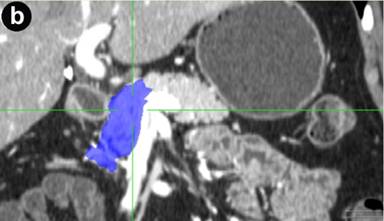

Preoperative computed tomography or magnetic resonance imaging were analyzed by the same radiologist who was blinded to the postoperative course. The volume of the pancreatic remnant was measured using a Voxar® 3D workstation (Barco NV, Kortrijk, Belgium) with 3D segmentation and volume calculation (Figures 1 and 2). The length and width of the resection plane were measured. The caliber of the main pancreatic duct was measured in the resection plane and in the head of the pancreas, as was the distance of the resection margin from the lesion.

Figure 2. Computed tomography of the pancreas showing 3D segmentation and volume calculation of the pancreatic remnant (in blue) in transverse (a.), coronal (b.), and sagittal (c.) images. |